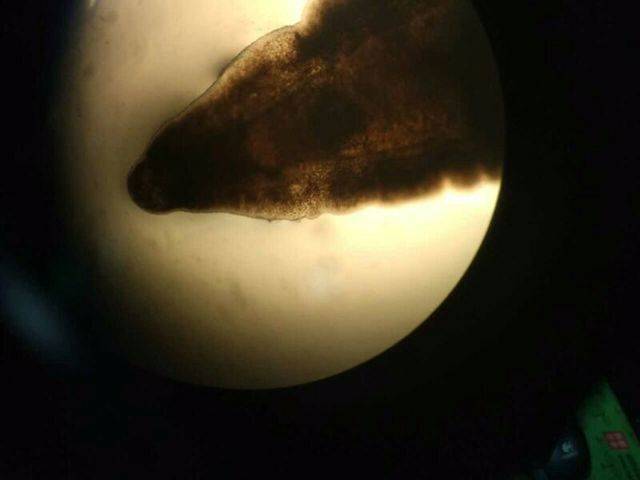

检验科医生在高倍显微镜下

发现肝吸虫虫卵

一见到这个小黑虫,凭直觉,有着20多年临床经验的楼洪萍医生便怀疑为肝吸虫。于是她把引流出的胆汁分装成近20支试管,进行离心沉淀后直接涂片镜检,在高倍显微镜下确认为肝吸虫的典型虫卵。杭州市疾控中心的检测明确了该诊断。